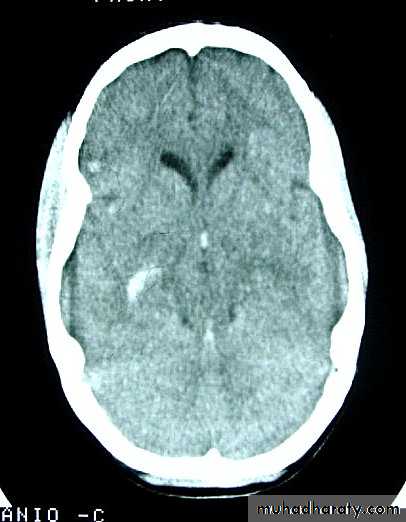

b. Subdural Haematoma

They are the most common intracranial mass lesions resulting from head trauma.

They are classified depending on how long they take to present clinically following the injury into:

Acute Subdural Haematoma: less than 3 days

Subacute Subdural Haematoma: 4-21 days

Chronic Subdural Haematoma more than 21 days.

Ct scan will show a concave hyperdence collection because blood follows the subdural space over the convexity of the brain.

CT scan: the acute clotted blood is initially appears white (hyperdence), but as it liquefies, it slowly becomes black (hypodense).